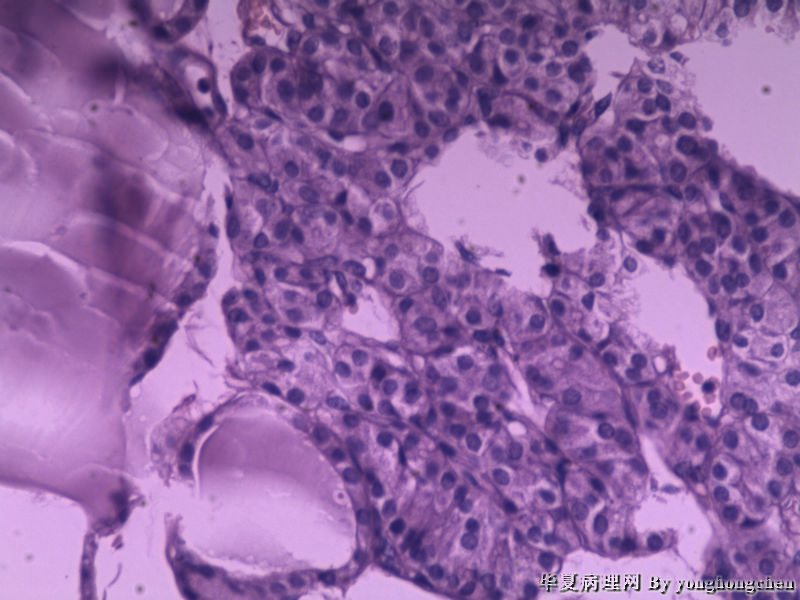

可不可能是嗜酸细胞腺瘤?

• 可不可能是嗜酸细胞腺瘤?图1

图1

女,22岁,左侧甲状腺肿物6*4*2厘米,包膜完整,切面灰红,质软。

有些地方像甲状旁腺

不是甲状旁腺,是甲状腺内的肿块。

图二间质内似有玻璃样物质,染PAS,排除HTT。

注意观察包膜侵犯情况。